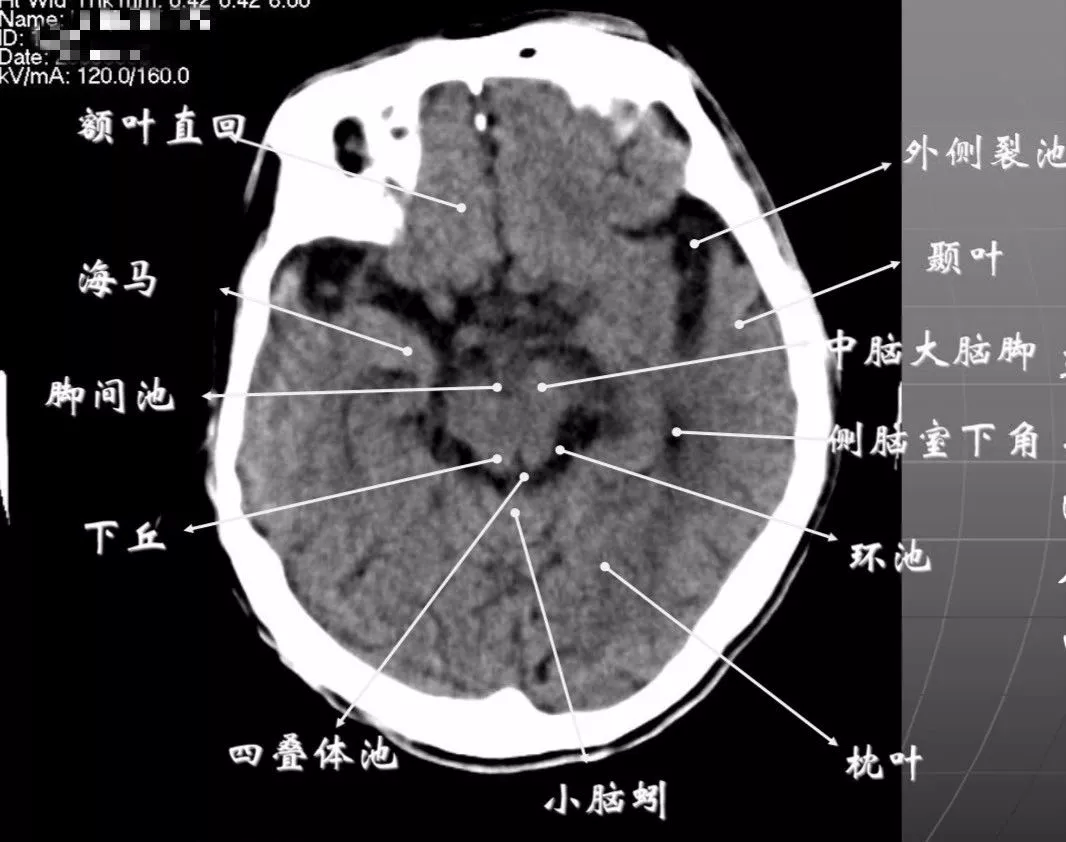

简明又详细的头部ct读片详解

简明又详细的头部ct读片详解收藏